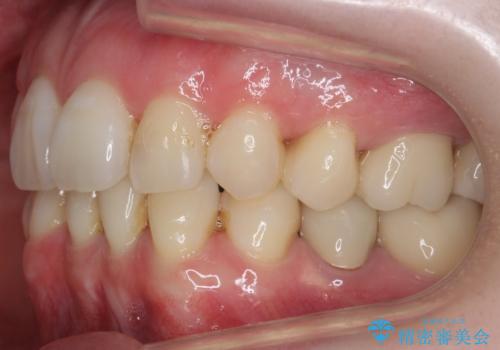

- 八重歯を主訴に来院。他院で全体ワイヤー矯正、4本抜歯で3-4年かかるかもしれないと説明を受けたとのこと。

そこまで時間がかかるのはどうかな、でも八重歯は気になるというご相談でした。

八重歯の部分は抜歯し、奥に入っていた前歯を前に移動させました。

下の前歯は生まれつき3本だったため、さらに2本下を抜くとなると3本少なくなってしまうため、下の前歯を一本お取りして最小限の抜歯としました。

上にはワイヤー部分矯正を行った後、インビザラインでマウスピース矯正を行っています。

今回は特に左上の犬歯は歯肉退縮して根が露出していたのもあり、抜歯をお勧めしました。